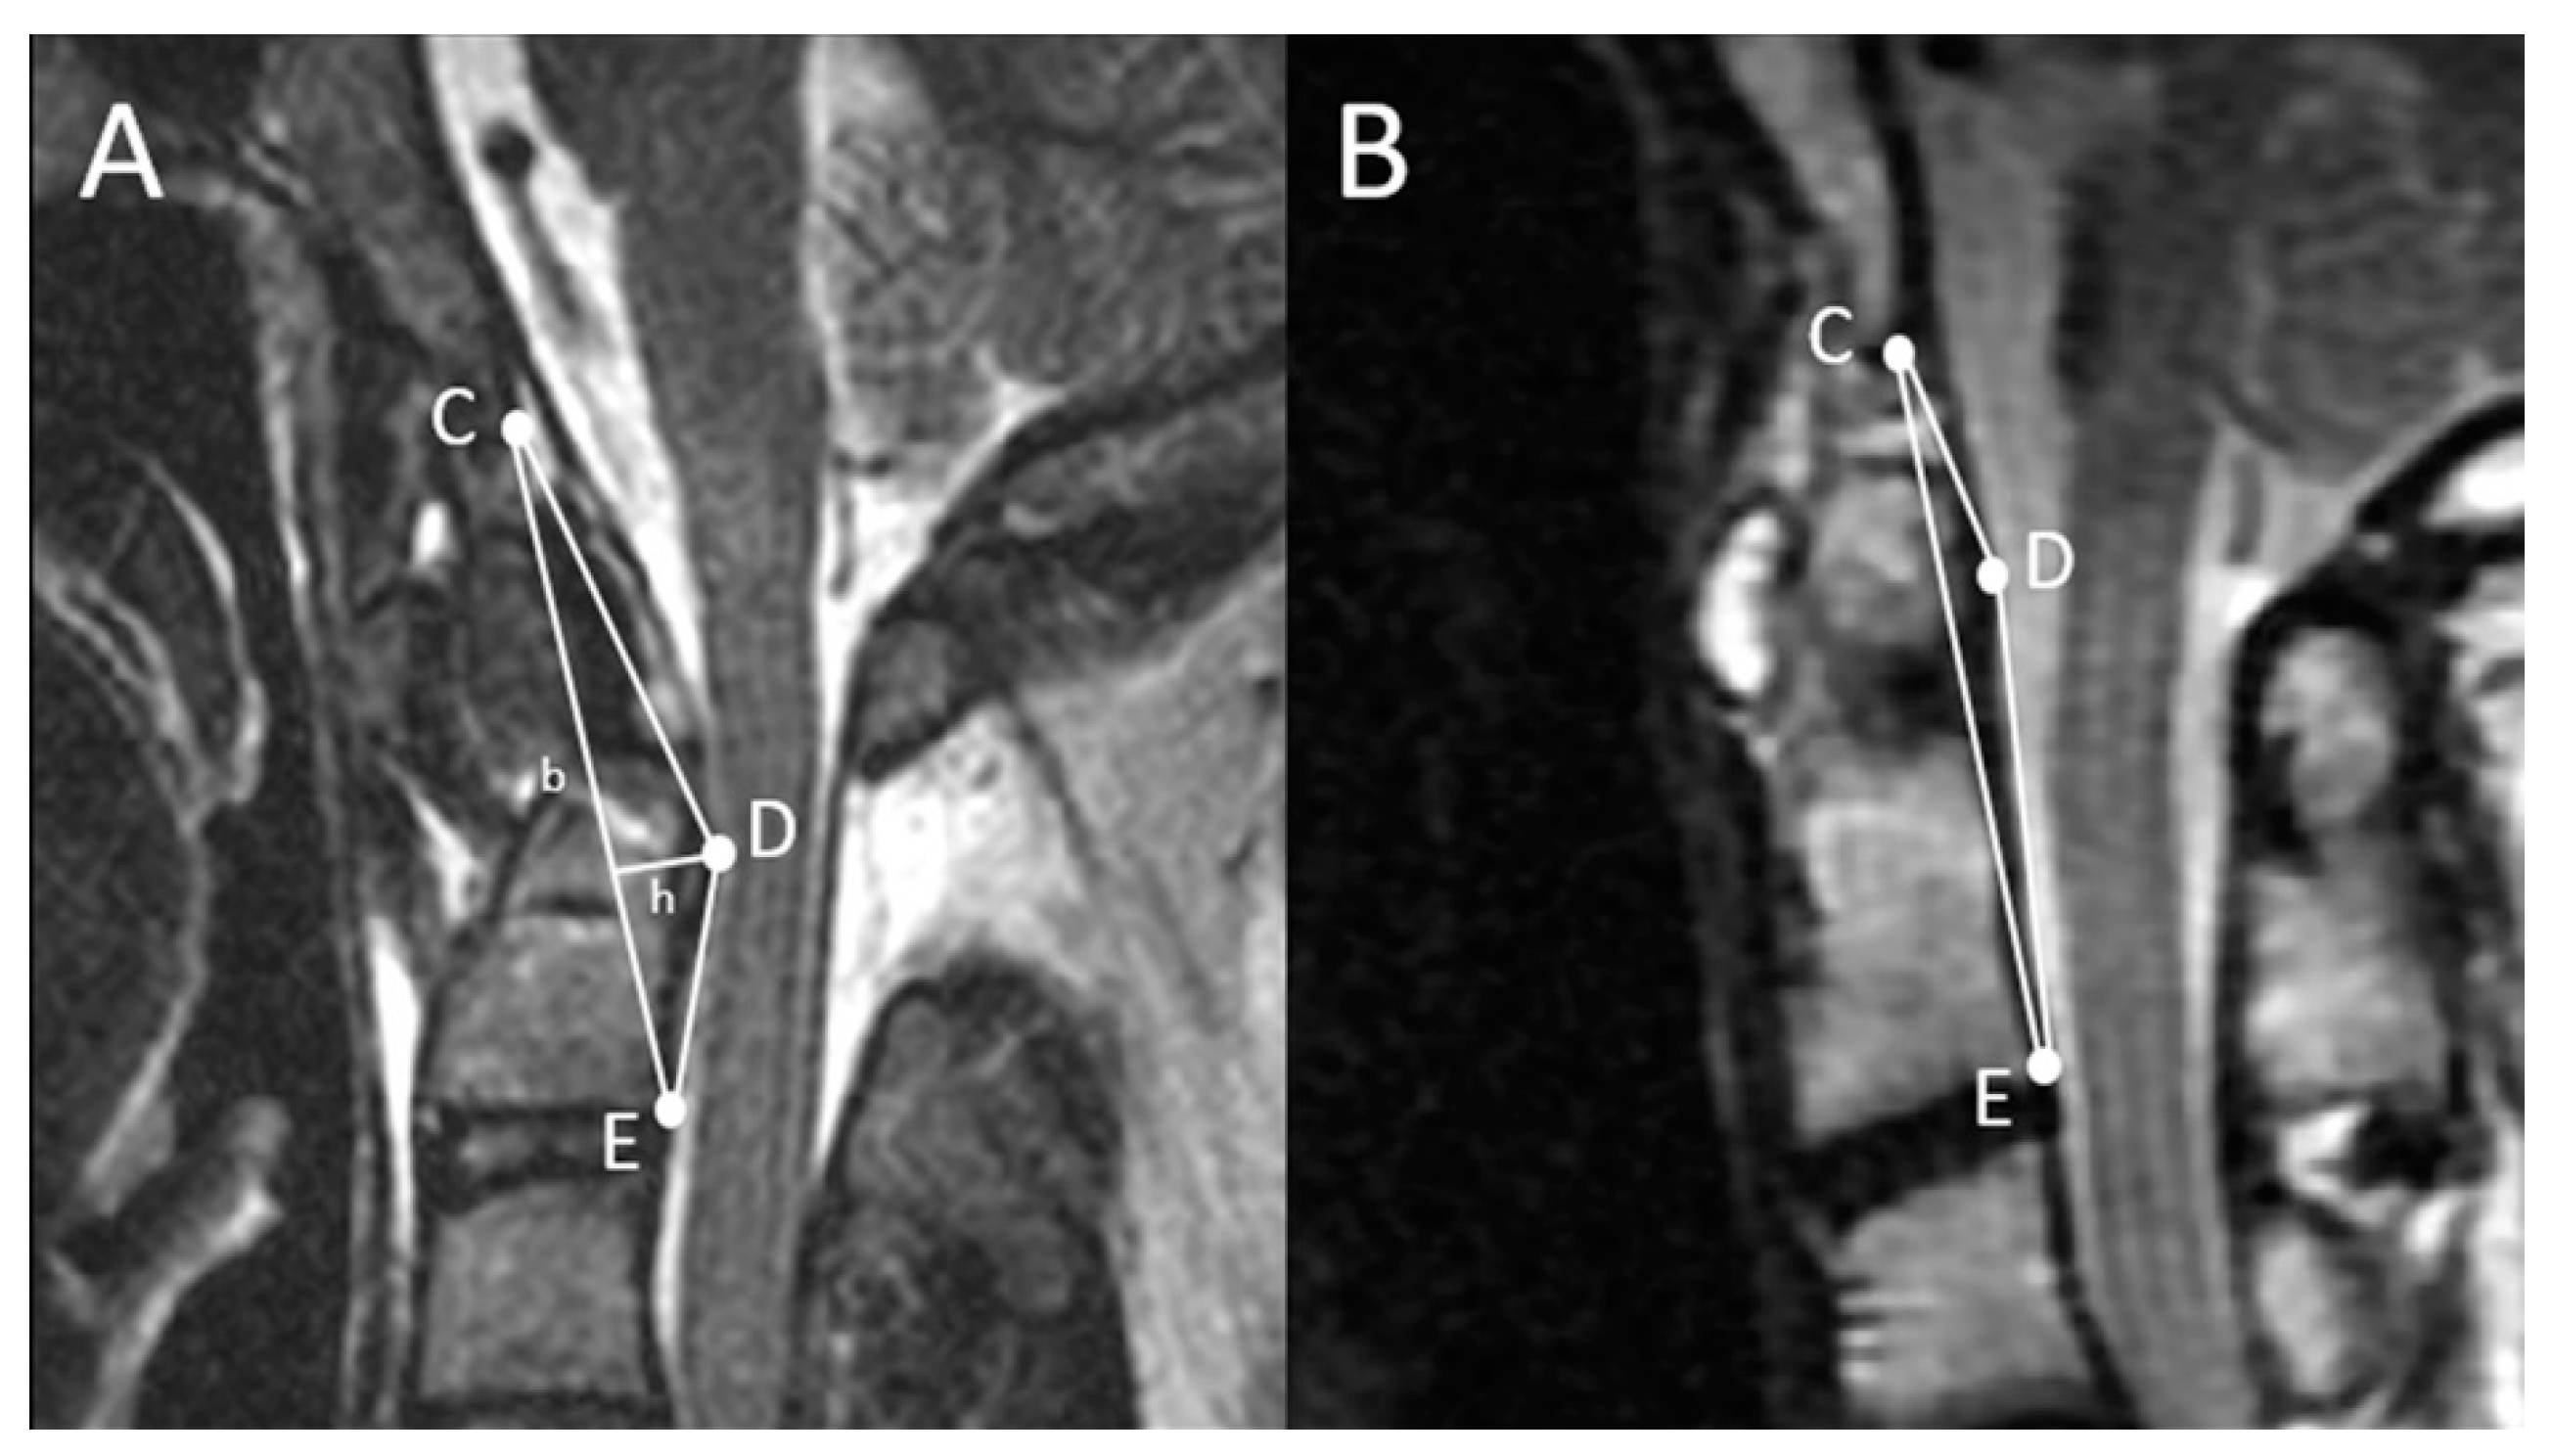

2.2. Radiographical Definition of the Triangular Area of the Cranio-Vertebral Junction (the TA of the CVJ)